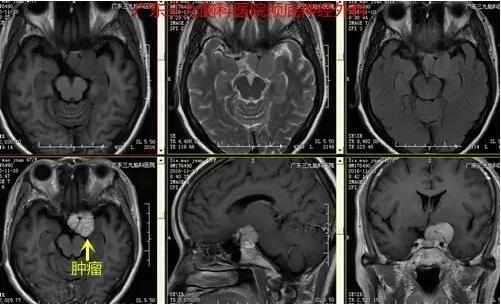

图3:术前MR提示左侧海绵窦区一团块状稍长T1稍长T2异常信号影,范围约2.8cm×2.8cm×2.3cm,增强后呈欠均匀明显强化,左侧颈内动脉终末段受包绕